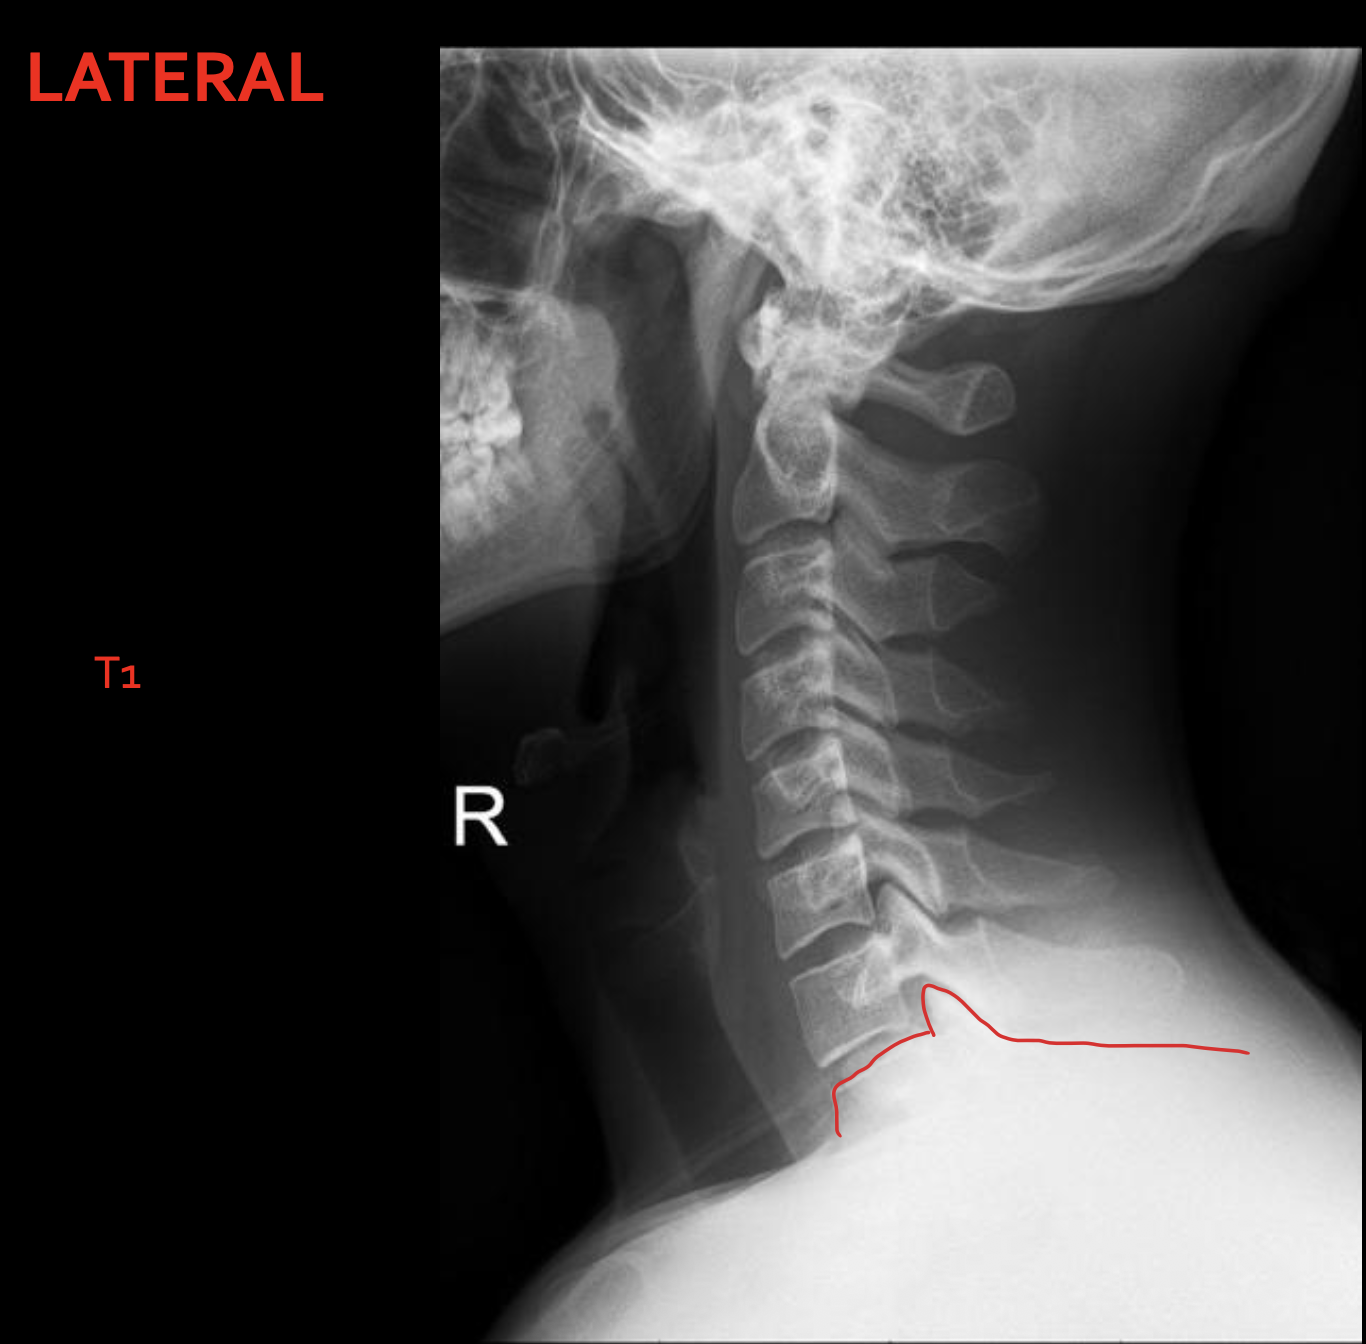

T1

1ST Rib